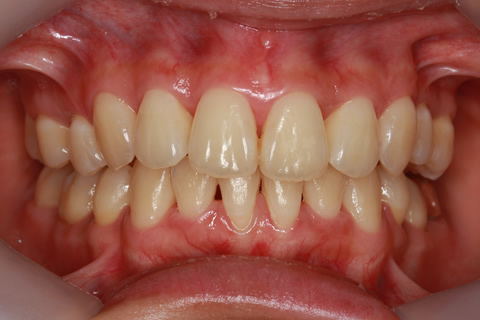

ハーフリンガル矯正2:上の歯のみ舌側矯正で治療(矯正期間18ヶ月)

- 年齢・性別

- 23歳女性

- 治療期間

- 1年6ヶ月

- 抜歯

- 上顎4番

- 治療費

- 110万円(税込み)

- 備考

- ハーフリンガル矯正

- 治療内容

- 上下前歯部凸凹の改善

- 施術の副作用(リスク)

- 裏側矯正の特性上、表側矯正と比較すると治療期間が長くかかる場合が多い。